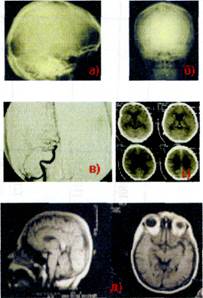

Тема:«Хирургические заболевания головы, лица, полости рта».

Рис. 1 Анатомия головного мозга.

Рис. 2 Методы исследования.

а и б –рентгенограмма черепа в двух проекциях,

в- ангиография,

г – компьютерная томография,

д- магнитно-резонансная томография.